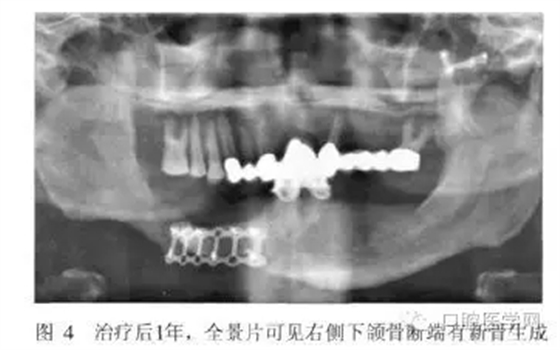

術后2周和半年進行兩次重襯。治療后半月、3月、6月、1年后復診,患者的頜面部外貌明顯改善,咀嚼功能提高,義齒使用效果良好(圖3)。全景片示骨斷端有新骨生成(圖4)。

從患者修復后1年的效果來看,義齒臨床效果良好,X線片示斷端骨密度升高。筆者認為對于類似長期骨愈合不良的斷端,通過適宜的功能刺激及義齒功能狀態(tài)下維持骨斷端的穩(wěn)定,可能有利于促進骨的生長和愈合。